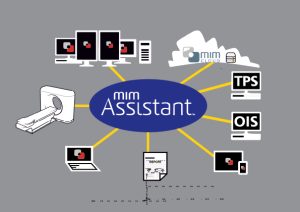

MIM Assistant ile Gelen Hasta Verilerini Otomatik İşleyin!

Klinik İş Akışının Yönetimi

MIM Assistant sayesinde kullanıcılar otomasyonun gücünü keşfedebilir ve kurallara dayalı bir ortamı kolayca oluşturarak gelen hasta bilgilerini otomatik işleyebilir ve MIM iş akışlarını çalıştırabilir.

Örnek olarak:

- Çalışma istasyonunuza geldiğinizde hemen bir CT’ye otomatik konturlama yapılabilir.

- Yapılar hasta listesine kaydedilebilir ve görüntüler inceleme amacıyla birleştirilebilir.

- Hastanın verileri alındıktan sonra plan raporları otomatik hazırlanabilir.

- Otomasyon kuralları ve filtreleri, kullanılmaya başlamalarından birkaç dakika önce seçilebilir ve test edilebilir.

Bu kişiselleştirilebilir özellik, kullanıcılara kendi otomasyon senaryolarını hazırlama olanağı sunmaktadır.

Veri Yönetimi

MIM Assistant,

- Veri saklama,

- Teşhis amaçlı görüntülerin otomatik sorgulanması,

- Otomatik yönlendirme ve getirme protokollerini içerir.

Ayrıca otomatik olarak MIMcloud™ sitesine gönderebilir ve sıkıştırılmış verileri aktarabilir, böylece gereksinim duyduğunuz verilere hemen erişebilirsiniz.

Kullanıcı Yönetimi

MIM Assistant, mevcut izinleri, profilleri ve oturum açma şifrelerini kullanarak LDAP/AD entegrasyonu yapabilir.

Bu entegrasyon, tek bir kişinin görmesini de destekler.

Farklı kullanıcıların tercihleri, iş akışları ve yetkileri yönetilebilir.

MIM’in görev listesi (Task List) işlevi,

- Planlama sürecinizi koordine etmek için kullanıcılara araştırmalar tahsis edebilir veya

- Araştırmalara statüler tahsis edebilir.